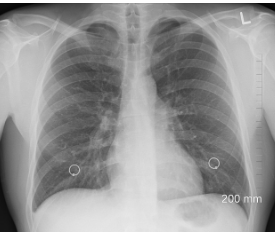

폐기흉(기흉)이란 무엇인가?

폐기흉은 폐의 공기주머니(폐포)가 터지면서 공기가 흉막강으로 새어 나와, 폐가 수축되는 질환입니다.

정상적으로는 폐가 공기를 들이마시고 내쉬면서 팽창과 수축을 반복하지만, 흉강 내 압력이 높아지면 폐가 펴지지 못해 호흡 곤란을 유발합니다.